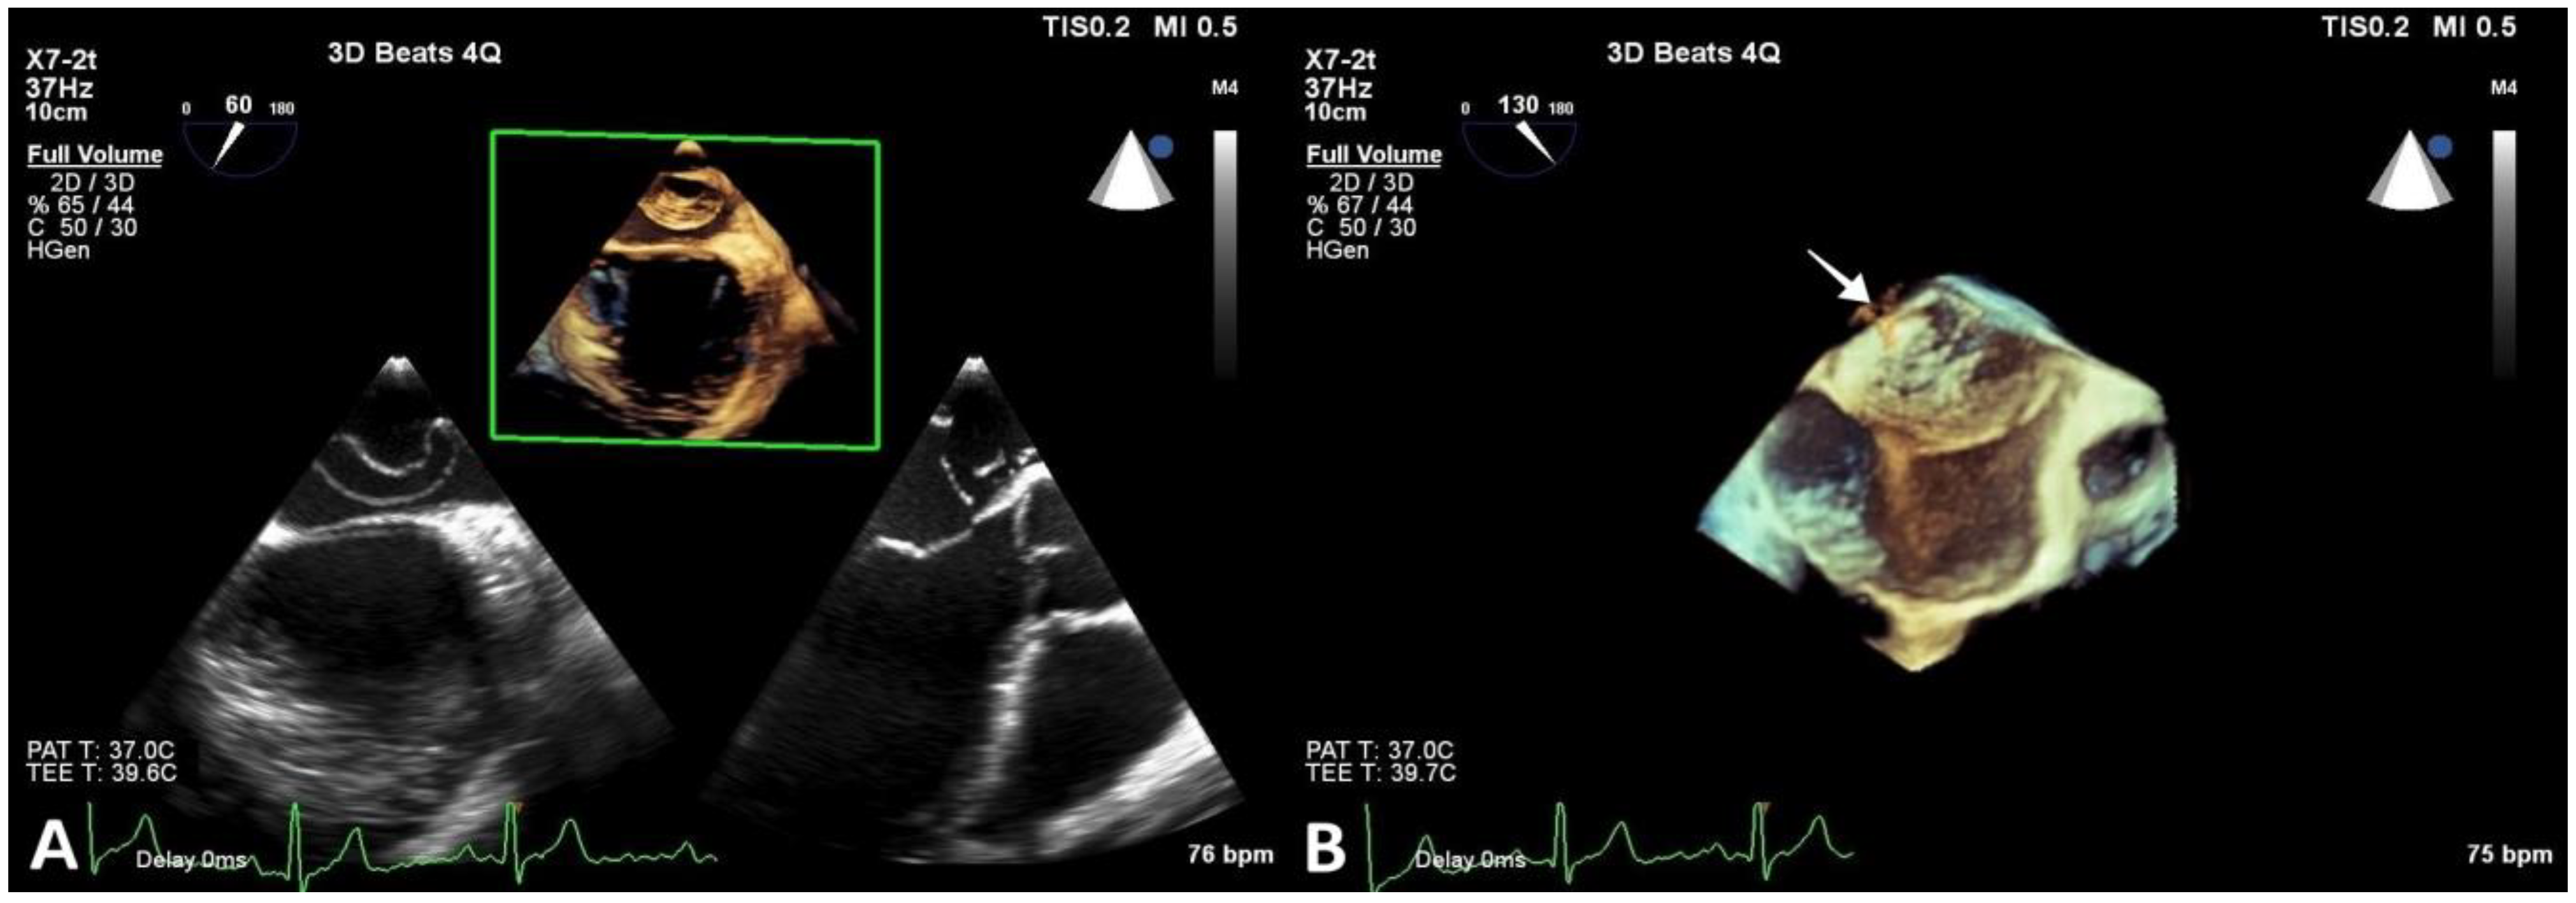

In order to better visualize the identified structure within the LA, a transesophageal echocardiography was performed. The membrane stretched out from the interatrial septum right beneath the foramen ovale to the lateral atrial wall above the LAA (Figure 3).

Figure 3.

Transesophageal echocardiography revealing CTS. (A) and (B) show 2D and 3D reconstructions visualizing the membrane and its fenestrations (arrow).

Multiple membrane fenestrations ensured the connection between the proximal and distal LA chambers. Color Doppler interrogation of the interatrial septum revealed PFO with minimal spontaneous left-to-right shunt (Figure 4).

Figure 4.

Transesophageal echocardiography revealing CTS. (A) Image showing openings in the CTS membrane (arrow). (B) PFO with minimal spontaneous left-to-right shunt (arrow).